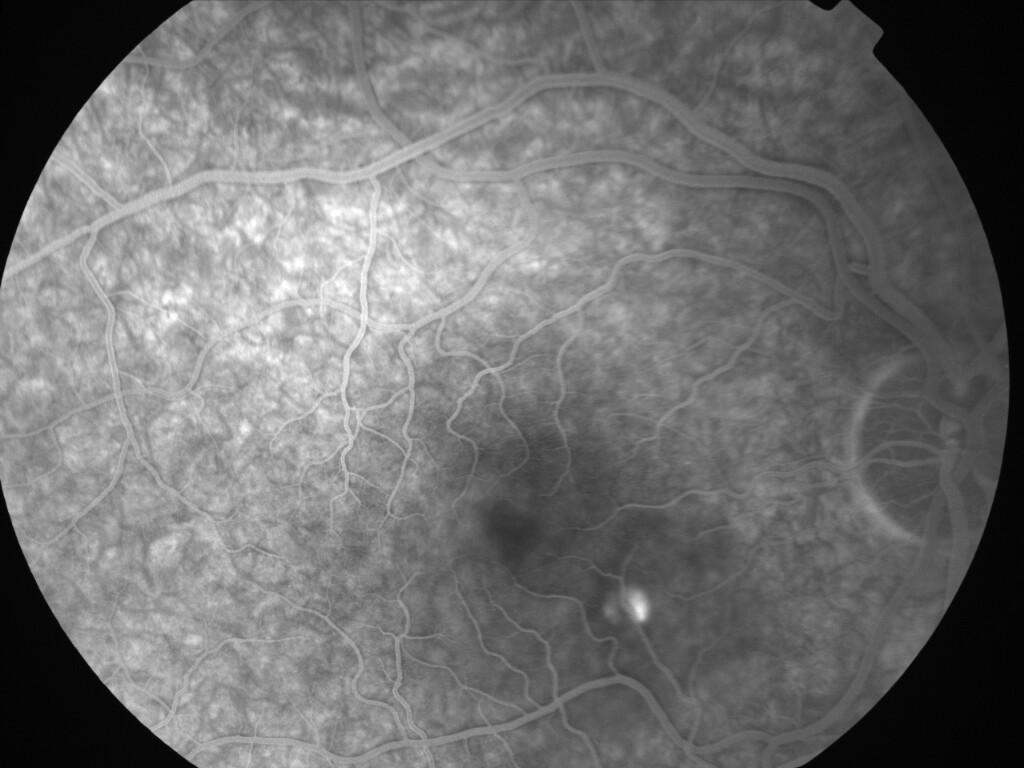

IM000003.jpg